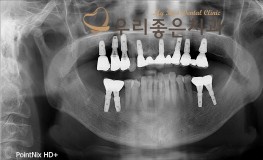

우리좋은치과 치아 상실로 인한 임플란트 보철 치료 (최** 2019.02.20~07..

No.347

임플란트

2019-11-25

1568